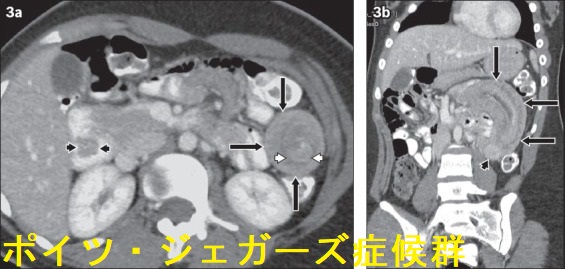

ポイツ・ジェガーズ症候群(Peutz-Jeghers症候群)は、常染色体性優性遺伝による癌抑制遺伝子Liver Kinase B1 (LKB1 or STK11)の機能喪失型変異が原因です。

- 小腸ポリポーシス(過誤腫ポリープ);1~3cmのポリープが小腸(特に空腸)に多発。有茎性・分葉状が多く、高頻度に再燃性腸閉塞・腸重積。慢性的な腸出血(下血)

- 悪性腫瘍の合併(50歳までに30%、70歳までに80%)

消化器癌が最多(60%);食道、胃、小腸、大腸、膵臓

甲状腺癌の合併

ポイツ・ジェガーズ症候群(Peutz-Jeghers症候群)に合併する甲状腺分化癌(甲状腺乳頭癌・甲状腺濾胞癌)は、通常のものと比べて悪性度が高いとされます(Exp Clin Endocrinol Diabetes. 2009 May;117(5):234-9.)。

生後16ヶ月の子供に発症したポイツ・ジェガーズ症候群(Peutz-Jeghers症候群)では、副腎皮質癌と甲状腺癌を同時に合併(J Pediatr Surg. 2011 Mar;46(3):570-3.)。

ポイツ・ジェガーズ症候群(Peutz-Jeghers症候群)でポリープ再発するたびに、低栄養・サルコペニア・低T3低T4症候群とポリープ摘出術による改善を繰り返した報告があります。「栄養状態並びに甲状腺機能を16年間観察したPeutz-Jeghers症候群の1例」(日本臨床外科学会雑誌 Vol. 76 (2015) No. 5 p. 1053-1058):ポリープの再発に伴い低栄養,サルコペニア,低T3低T4症候群をきたし、ポリープ摘出術で改善する病態を繰り返すそうです。